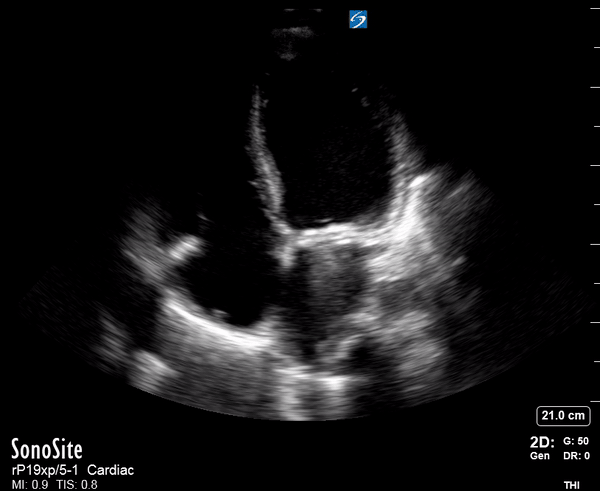

THE VIEWS

The PLAX view is versatile and allows the recognition of multiple landmarks, making it good for visual estimation of LV contractility. It is essential to optimize the view ensuring a true sagittal long axis, as being oblique to the LV chamber may underestimate its size and overestimate its emptying. The PSAX view at the level of the papillary muscles reveals the entire muscular circumference and concentric squeeze of the LV. It is useful to estimate both global function and focal wall motion abnormalities. The A4C view, although technically challenging, provides good insight into the global myocardial function and chamber size.

LV CONTRACTILITY

Qualitative assessment of the LV and visual estimation of Ejection Fraction is based on three parameters:

Endocardial excursion.

Myocardial thickening.

Movement of the anterior leaflet of the mitral valve.

A qualitative assessment is typically categorised as:

Normal (LVEF 50-65%)

Moderately Depressed (LVEF 30-50%)

Severely Depressed (LVEF < 30%)

Hyperdynamic (LVEF > 65%)

SIGNIFICANTLY IMPAIRED / DILATED LV

A severely depressed LV contractility, particularly when paired with a plethoric IVC or lung B-lines, indicates systolic heart failure. Chronically raised afterload can lead to severe dilation of the LV.

In contrast, hyperdynamic states are associated with decreased afterload and are classically found in patients with sepsis or severe hypovolaemia. A hyperdynamic heart should be accompanied by a small, collapsing IVC. Moreover, is essential to remember that tachycardic is not the same as hyperdynamic, as the latter is a measure of contractile activity and emptying. A tachycardic heart is not necessarily hyperdynamic.

E-POINT SEPTAL SEPARATION

Active movement of the MV anterior leaflet during diastole, so it nearly touches the septum, correlates with good LV filling and ejection fraction. This can be assessed objectively by measuring the E-point septal separation (EPSS), which is the distance between the septum and the mitral anterior leaflet either in B-mode or M-mode. EPSS < 7mm is considered normal. EPSS is a good surrogate measure of ejection fraction, but it should be used with caution, as septal hypertrophy and mitral valve stenosis can lead to wrong estimations. In the PLAX view, it is important to have the septum lying horizontally flat on the image, as an oblique orientation may result in an overestimation of the EPSS.